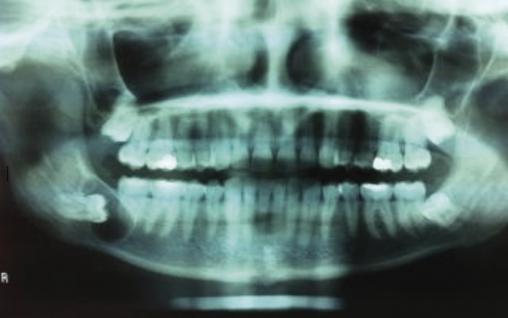

Lors de sa visite d’incorporation, un militaire de 24 ans réalise un panoramique dentaire systématique. Il n’a aucun symptôme, et l’examen clinique effectué par le dentiste est sans particularités.

La radiographie montre une formation kystique en regard de la dent n° 48 (fig. 1 ).